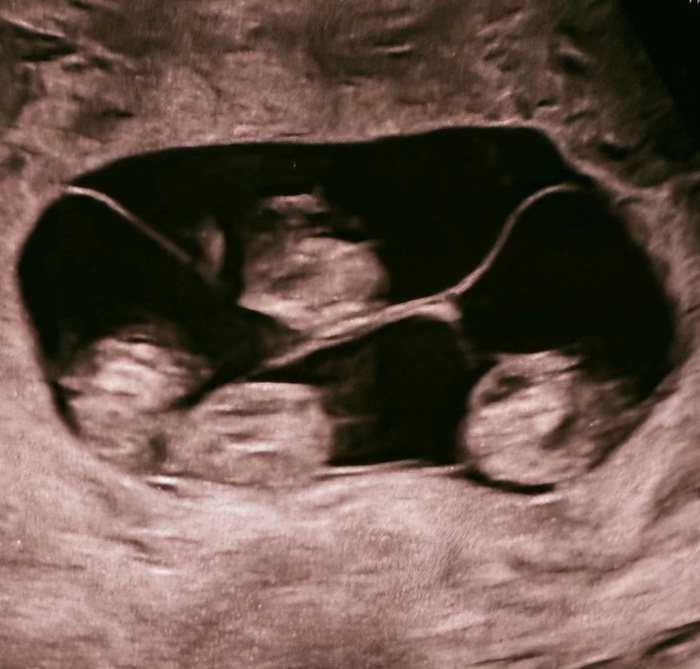

Один случай на 15,5 миллионов: в Петербурге родились первые в России однояйцевые четверняшки

В роддоме №10 Петербурга случилось чудо, которое раньше в нашей стране не случалось. Женщина по имени Мария родила четырёх девочек — и все они однояйцевые близнецы. Одна оплодотворённая яйцеклетка разделилась на четыре самостоятельных организма — дети получаются одного пола, с одинаковой внешностью и группой крови. Настоящие копии. Как объяснил заместитель главврача Евгений Михайлин, монохориальная (с одной плацентой) четверня встречается один раз на 15, 5 миллиона родов. И Мария доносила их до 32 недель — для четверых это отличный срок. Вес малышек — от 1360 до 1640 граммов, рост — от 37 до 41 сантиметра. Петербург уже знаменит одной четверней (правда, не однояйцевой). Но эта — первая и уникальная. Один случай на 15 миллионов. Добро пожаловать в мир, близняшки! Пост автора truekpru. Читать комментарии на Пикабу.

Как объяснил заместитель главврача Евгений Михайлин, монохориальная (с одной плацентой) четверня встречается один раз на 15, 5 миллиона родов. И Мария доносила их до 32 недель — для четверых это отличный срок. Вес малышек — от 1360 до 1640 граммов, рост — от 37 до 41 сантиметра.